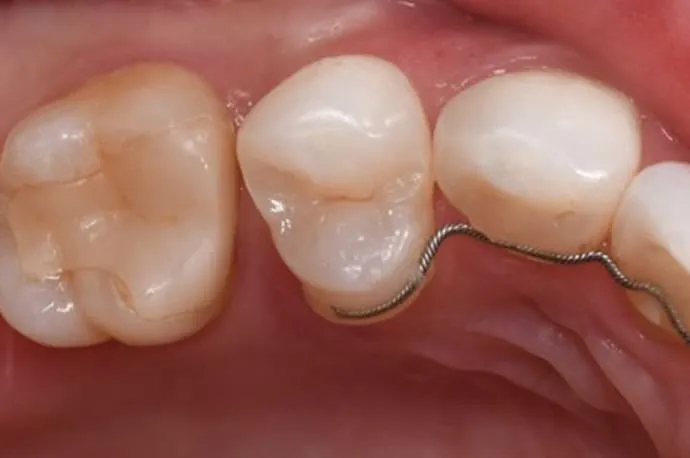

中程度の虫歯:詰め物(インレー)

| 治療回数 | 2回 |

| 術後の痛み | 虫歯が深い場合、冷たい物でしみたり、噛むと痛みが出ることがあります。型採りから詰め物完成まで仮の蓋で過ごすため、噛み合わせによって痛みが出ることもあります。痛みが強い場合や続く場合は追加治療を行うことがあります。 |

虫歯を除去した後、範囲が大きい場合は樹脂では強度不足になるため型採りを行います。歯型は歯科技工士に送り、模型をもとに詰め物を作成。問題がなければ、次回の来院時に装着します。

詰め物には、保険診療と自費診療の素材がいくつかあります。それぞれ特徴が異なりますので、患者さまのお口の状態に合った最適な材質についてはご相談ください。